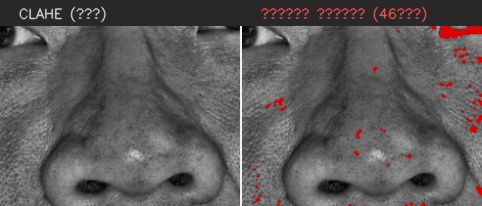

이마

유효 주름 수 4개 · 주 방향 가로

상위 깊이(평균 상위3) 0.320 mm

| # | 길이(mm) | 깊이(mm) | 유효 판정 근거 |

|---|---|---|---|

| 1 | 8.63 | 0.110 | 대표 깊이 0.110 mm가 이 부위 최소 깊이 0.100 mm 이상이고, 유효 길이 8.63 mm가 최소 길이 5.00 mm 이상이어서 노이즈·미세선과 구분되어 유효 주름으로 집계되었습니다. |

| 2 | 10.47 | 0.161 | 대표 깊이 0.161 mm가 이 부위 최소 깊이 0.100 mm 이상이고, 유효 길이 10.47 mm가 최소 길이 5.00 mm 이상이어서 노이즈·미세선과 구분되어 유효 주름으로 집계되었습니다. |

| 3 | 5.76 | 0.322 | 대표 깊이 0.322 mm가 이 부위 최소 깊이 0.100 mm 이상이고, 유효 길이 5.76 mm가 최소 길이 5.00 mm 이상이어서 노이즈·미세선과 구분되어 유효 주름으로 집계되었습니다. |

| 4 | 14.61 | 0.477 | 대표 깊이 0.477 mm가 이 부위 최소 깊이 0.100 mm 이상이고, 유효 길이 14.61 mm가 최소 길이 5.00 mm 이상이어서 노이즈·미세선과 구분되어 유효 주름으로 집계되었습니다. |